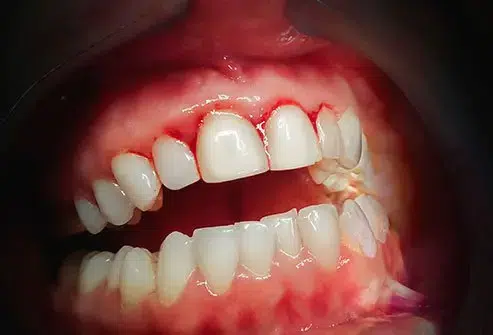

In acute ulcerative gingivitis, the gum tissue appears swollen, red, and painful, with a shiny surface and bleeding when gently examined. It rarely causes spontaneous bleeding and is usually not painful in its mild forms; however, in acute cases it can be quite uncomfortable.

This type of gingivitis is caused by the buildup of dental plaque, a sticky film of bacteria that forms on the teeth. It is characterized by red, swollen gums that may bleed easily, especially during tooth brushing or flossing.

Acute gingivitis is a serious form of gum inflammation and requires prompt treatment. It can rapidly lead to:– Marked redness and swelling of the gums – Gum pain and tenderness – Bleeding gums, especially while brushing or eating – Bad breath (halitosis) or a bad taste in the mouth – Gum recession in some cases – Difficulty chewing due to painThis condition is often seen in smokers, but it is also associated with severe psychological or physical stress. Acute gingivitis has also been linked to systemic health problems such as heart attacks, lung diseases, and other systemic conditions.